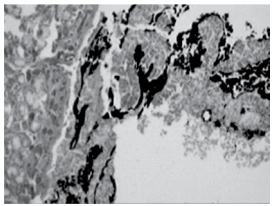

Indivíduo vítima de homicídio por arma de fogo teve seu corpo queimado com a finalidade de ocultação do corpo e, consequentemente, do crime. Durante a necropsia, foi colhido fragmento de via aérea (traqueia) cujo exame histopatológico mostrou presença de material enegrecido, compatível com fuligem, aderido ao epitélio de revestimento da mucosa, conforme mostra a figura.

enunciado 723177-1

É correto afirmar que